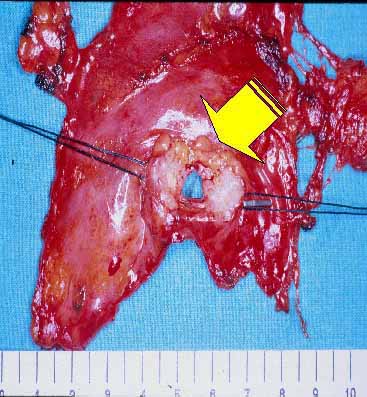

The lower half of the gland is then retracted upward and the thymic veins, usually two or three, are identified clipped and divided (Figure 5). Subsequently, the dissection proceeds cephalad, superior to the innominate vein, into the lower cervical region. The superior horns are progressively dissected free by blunt maneuvers with the aid of gentle traction applied downward on the thymus. In this way, even long and thin upper horns can be dissected en bloc with the rest of the gland. The intact thymus is extracted in a retrieval bag through the most anterior port and is examined to ensure that the whole gland has been removed (Figure 6).

View image largerFigure 5. The innominate vein has been skeletonized and a thymic vein is being clipped. View image largerFigure 6. Resected specimen comprising the whole thymic gland characterized by a large left inferior horn.